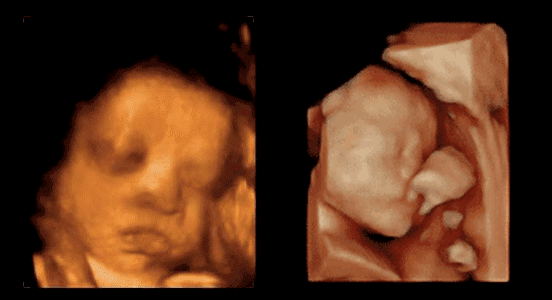

四维彩超可以看见什么?

为什么有些宝宝的四维彩超照片看起来不漂亮